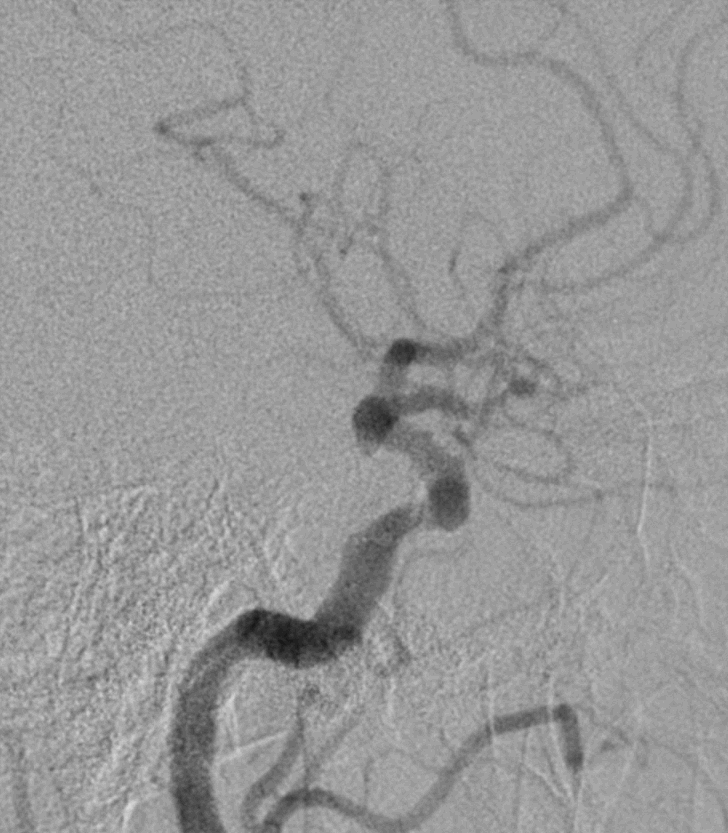

正侧位造影

3D旋转造影